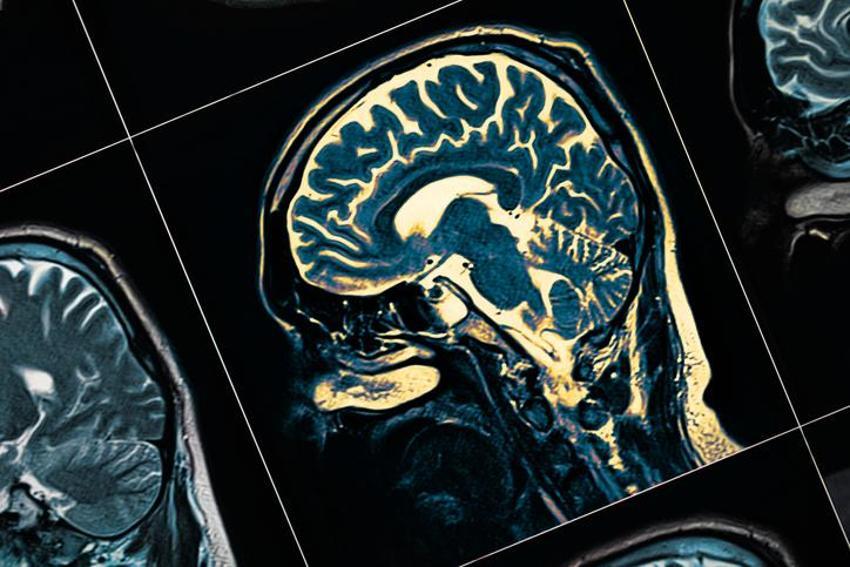

Gün içinde yaşanan unutkanlığın sebebi bazen strese bağlıdır ancak alzahimer gibi ciddi bir hastalığın belirtilerinden biri olduğu için ihmal edilmemelidir. Hafıza ile ilgili yaşanan problemler kişiden kişiye farklılık gösterse de ilerlediğinde hayatı zorlaştıran bir durumdur. Yapılan araştırmalara göre, bazı besinler unutkanlığı gideriyor, hafıza problemlerini ortadan kaldırarak alzahimer hastalığını önlemeye yardımcı oluyor. Peki, hangi besinler unutkanlığı gideriyor? İşte alzahimer hastalığının doğal ilacı olarak anılan en şifalı besinler...

Kısa süre öncesine kadar hafızanın yaşla birlikte zayıflaması normal olarak kabul ediliyordu. Ancak günümüzde, hayat boyu sürdürülen doğru beslenme ve beyni çalıştıran egzersizlerle yaşlılığa bağlı hafıza kaybının azaltılabileceği biliniyor.

Yaş alırken tüm diğer organlarımız gibi beynimizde eskir ve gençlik dönemindeki kadar keskin bir hafızamız olmayabilir. Fakat doğru yiyecekleri seçerek yaşlanmanın getirdiği bu olumsuz etkileri en az düzeyde tutmak mümkün.